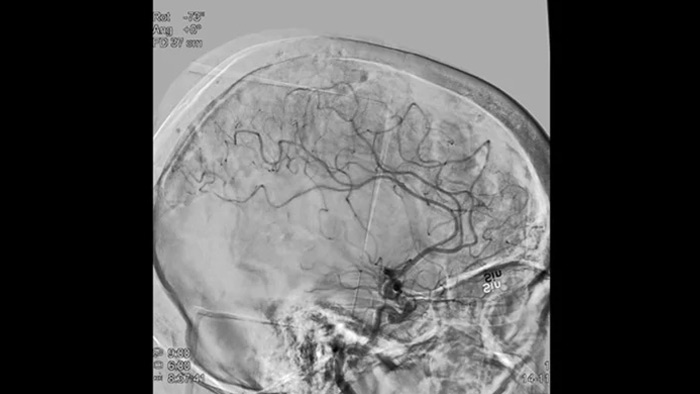

Sharp images with 2D DSA with ClarityIQ technology

2D DSA with ClarityIQ technology

ClarityIQ applies Automatic Motion Compensation during real-time DSA to maintain sharp images of the vessels. This supports confident decision making throughout stroke procedures.

DSA visualization

High quality DSA visualizations allow you to assess if you have retrieved the complete clot and if pieces of clot have been dispersed distally in the brain. You can check the restoration of blood flow to the penumbra and check for peri-procedure bleedings.